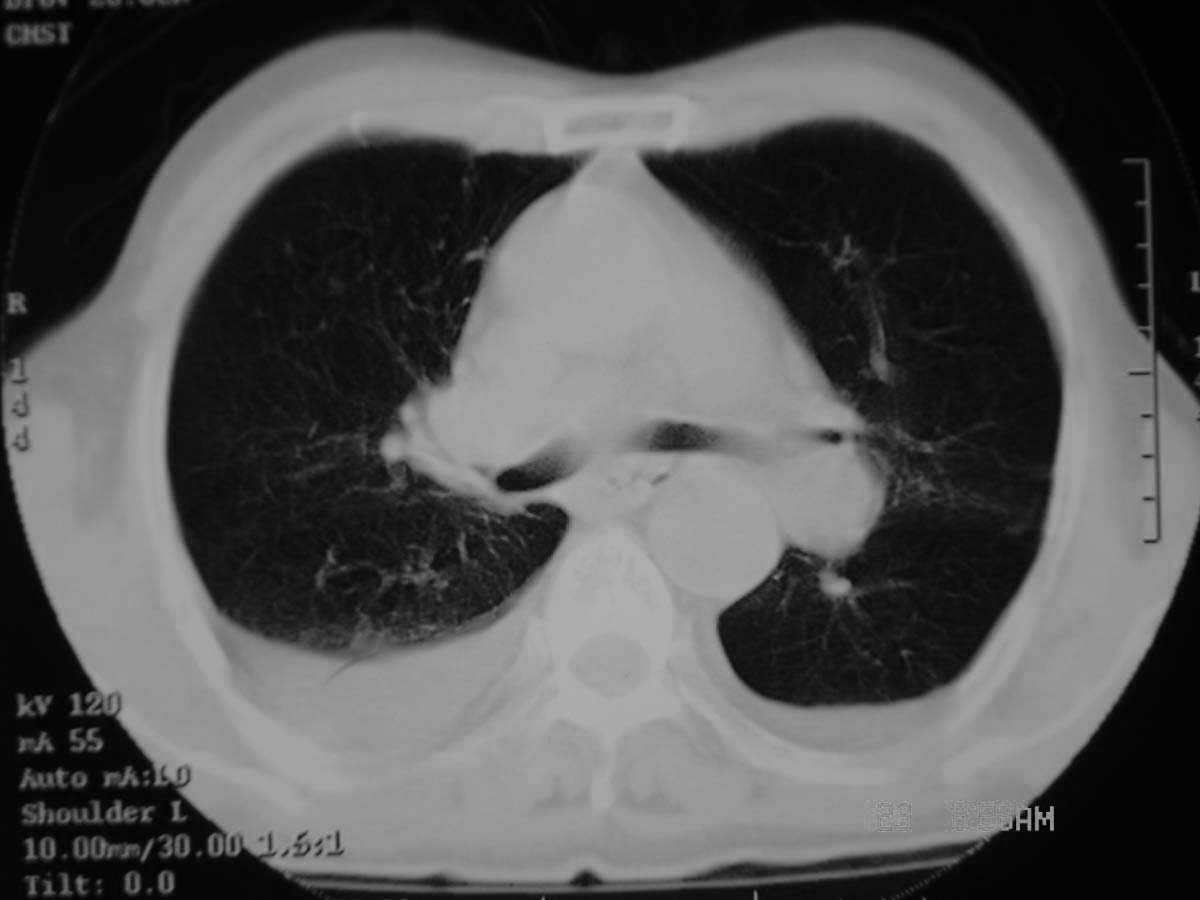

以下是引用守望可可西里在2006-11-23 14:33:00的发言:[br][br] 糖尿病病人很容易继发结核,病人又有双侧胸膜增厚、粘连、胸腔积液以及双上肺的斑片状、条索状影结核病灶影,以一元论考虑,右下肺病变首先考虑干酪性肺炎,可以正规抗炎治疗后复查,排除一般的肺炎。